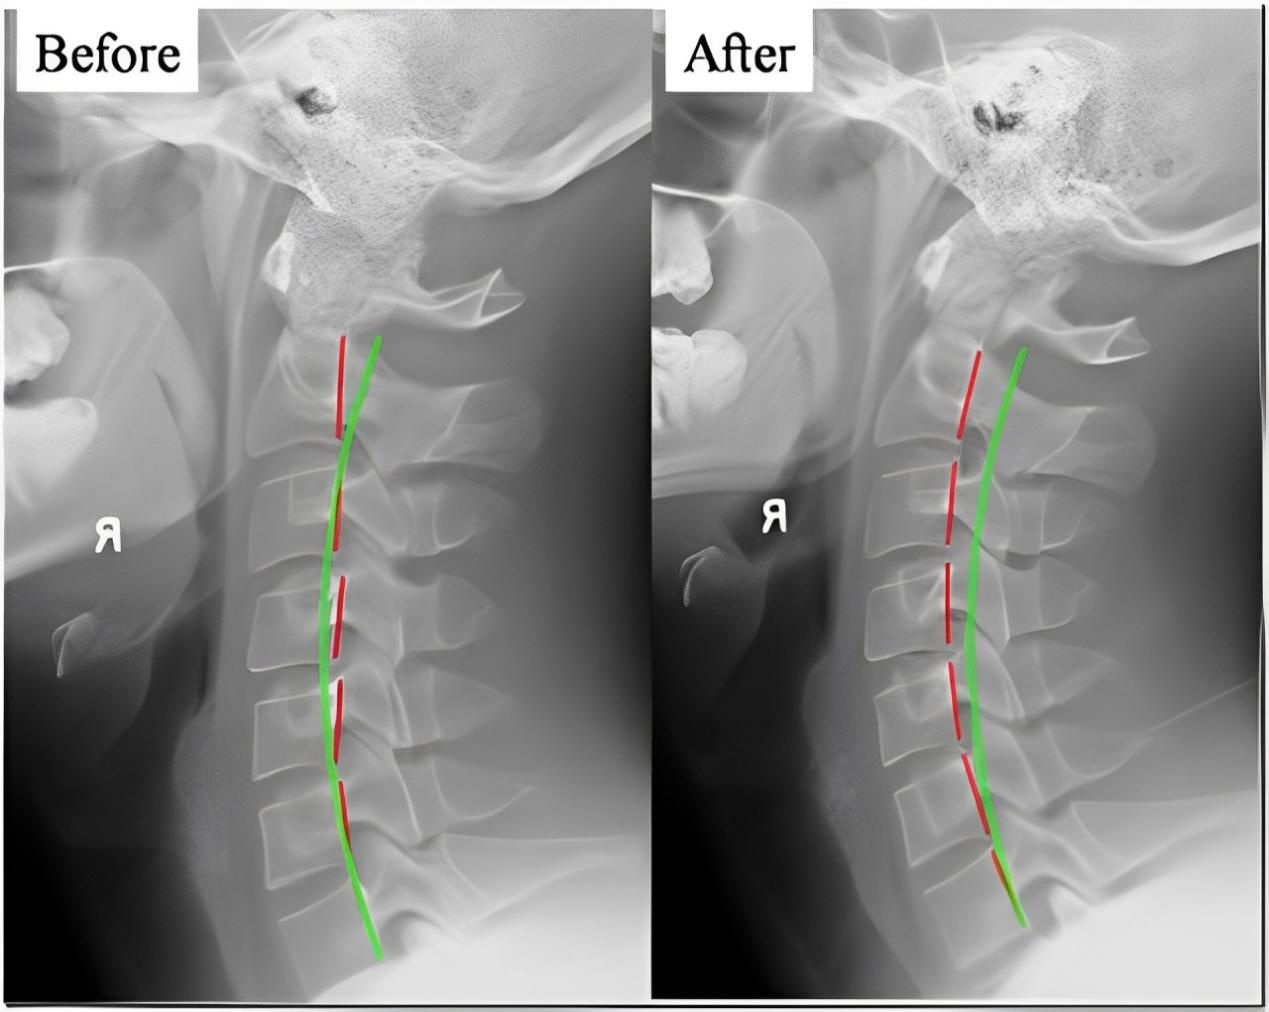

四、 恢復脊椎自然曲度

脊椎整復床的獨特設計能夠幫助恢復脊椎的自然曲度,改善脊椎側彎和不良姿勢,讓您重獲健康體態。

五、矯正完和矯正后的對比案例: